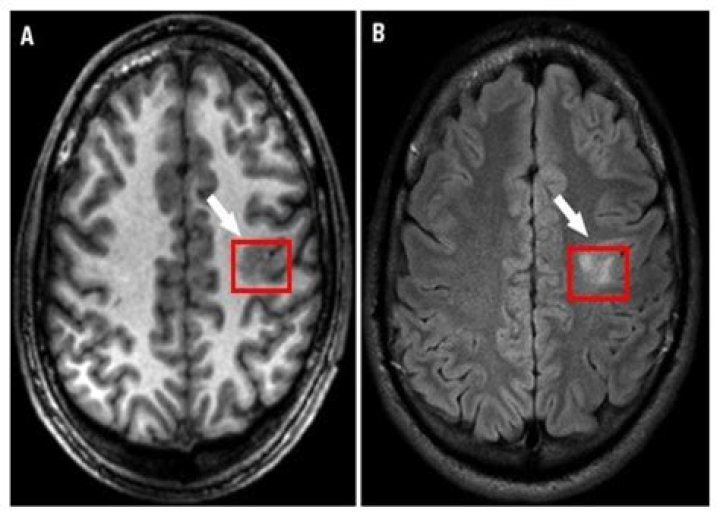

Vestibular schwannoma is one of the common benign tumors that arise from the vestibulocochlear nerve. It is termed intralabyrinthine schwannoma (ILS) when the tumor is originated from the Schwann cells surrounding the terminal branch of the vestibulocochlear nerve inside the membranous labyrinth (1, 2).

Intralabyrinthine schwannoma’s are a rare variant of an inner ear tumor — acoustic neuromas. Acoustic neuromas (follow link for far more information), also known as vestibular schwannomas, are non-malignant tumors of the 8th cranial nerve.

intralabyrinthine schwannomas. Schwannoma is a benign neoplasm of the nerve sheath and is the most common neoplasm of the IAC and CPA. “Acoustic” schwannomas most often arise from the vestibular division of the vestibulocochlear nerve.

Schwannoma is a benign neoplasm of the nerve sheath and is the most common neoplasm of the IAC and CPA. “Acoustic” schwannomas most often arise from the vestibular division of the vestibulocochlear nerve. These tumors arise from the perineural Schwann cells surrounding the vestibular and cochlear nerves.